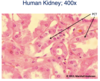

Identify:

Simple cuboidal epithelium.

* Photomicrograph of kidney tubules

Simple cuboidal epithelium